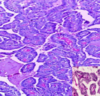

Q

Adenomatous polyp

Proliferated acini (glands) variable in size and shape and lined by columnar mucin secreting cells. Some are lined by dysplastic epithelium shows mucin depletion and elongated pseudostratified nuclei.

Benign

Can turn cancerous so yes